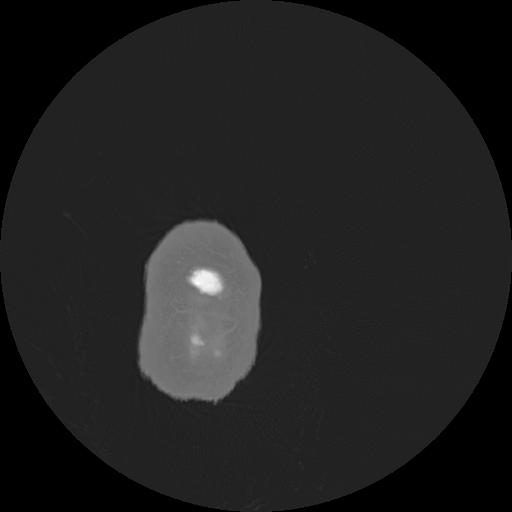

7 HUESO,,Vol,0.5,HUESO,,